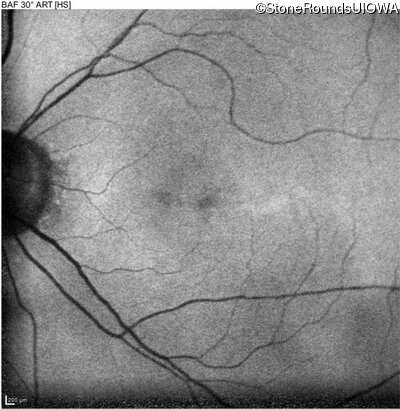

This 70 year old woman first noticed some reduction in visual acuity in both eyes at age 45. Her visual acuity had been previously normal.

The clinical features favoring the diagnosis of RP1L1-associated occult macular dystrophy include: reduced acuity with a near-normal ophthalmoscopic appearance, a history of normal acuity in childhood; and, a "moth-eaten" appearance of the macular ellipsoid zone on OCT.